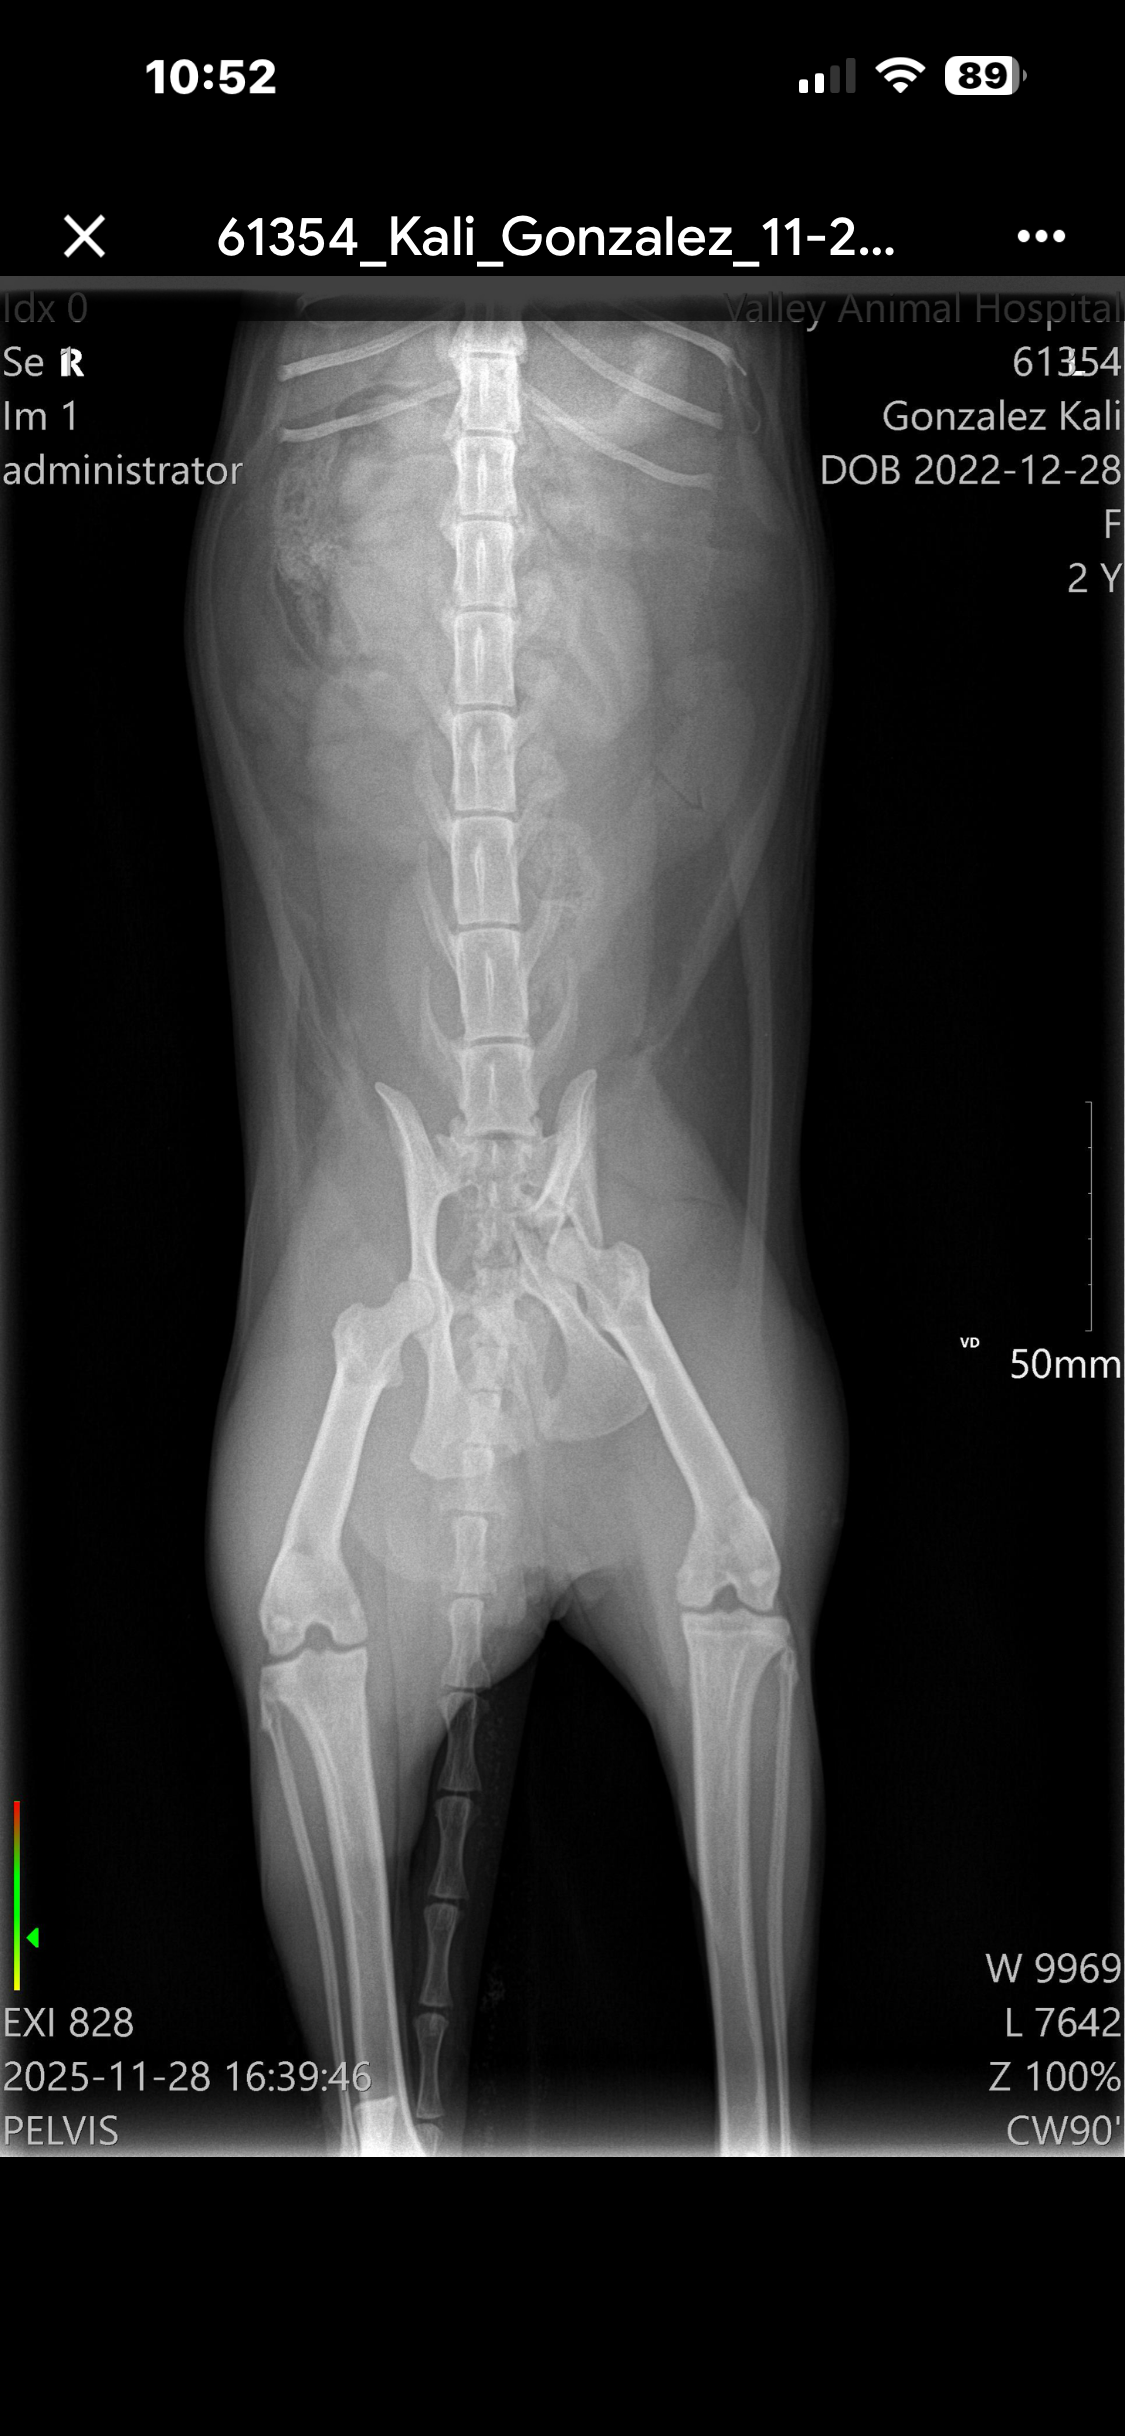

Recently, Kali chewed through the fence of her cat patio and escaped. When I found her, her leg was numb. At the vet, I learned she suffered a severe pelvic fracture—an injury that won’t heal on its own and requires surgery. Without it, she may never be able to move her right leg again.

Kali is having part of her pelvis removed, and it will be replaced with a flexible metal plate. It’s a major surgery — and, unfortunately, it comes with a major price tag.